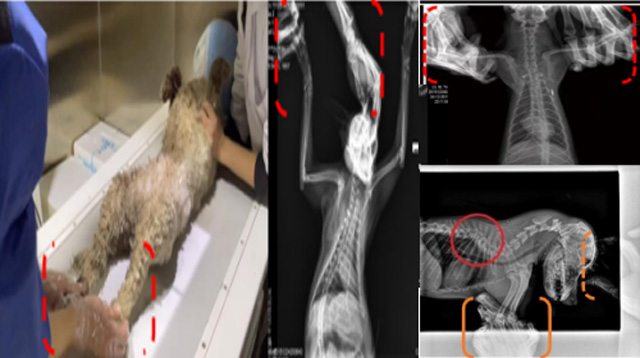

現(xiàn)在寵物醫(yī)療設(shè)備得到高速發(fā)展,現(xiàn)在有越來越多的寵物診療機(jī)構(gòu)配置X射線裝置如寵物DR。寵物骨折或者有其他疾病不能通過直觀看出來的。寵物診所醫(yī)生都會使用寵物DR來做輔助檢查。但是有時候?qū)櫸镝t(yī)生沒有加強(qiáng)防護(hù),就在寵物DR室給寵物拍X片做檢查。這樣也是會受到X射線的輻射。因?yàn)閄射線上崗是屬于職業(yè)病危害崗位。長期的輻射會對人體造成一定的危害。寵物醫(yī)生也需要接受X射線照射的上崗前都必須進(jìn)行放射工作人員的職業(yè)健康體檢。體檢不合格的話是不能擔(dān)任放射工作的。未經(jīng)上崗前職業(yè)健康體檢的勞動者從事接觸職業(yè)病危害作業(yè)的行為,已經(jīng)違反了《中華人民共和國職業(yè)病防治法》第三十五條規(guī)定,依據(jù)《中華人民共和國職業(yè)病防治法》第七十五條規(guī)定,需要進(jìn)行整改罰款。開展寵物放射診療活動,在日常工作中,對本機(jī)構(gòu)的X射線危害的職業(yè)病防治,需要知道并做到以下內(nèi)容: